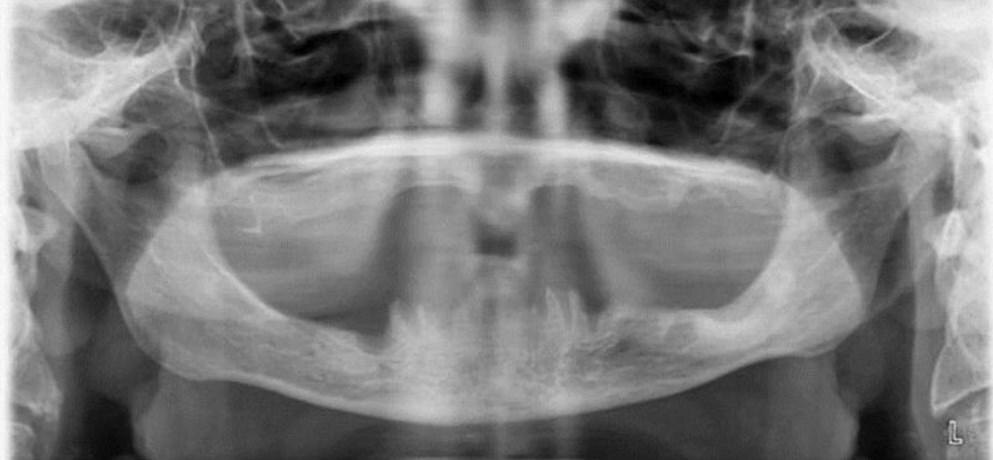

Полная адентия на снимке

Врожденная адентия — это аномалия развития зубочелюстной системы, при которой у ребенка отсутствуют зачатки одного или нескольких зубов с рождения. Это означает, что такие зубы никогда не прорежутся, поскольку их просто нет в челюсти.

Адентия бывает:

⚠️Частичной — отсутствует 1-5 зубов. Чаще всего не хватает вторых резцов, пятерок и, в случае с постоянным прикусом, зубов мудрости.

⚠️Множественной — не сформировались зачатки 6 зубов и более.

⚠️Полной — отсутствуют все молочные и постоянные зубы.